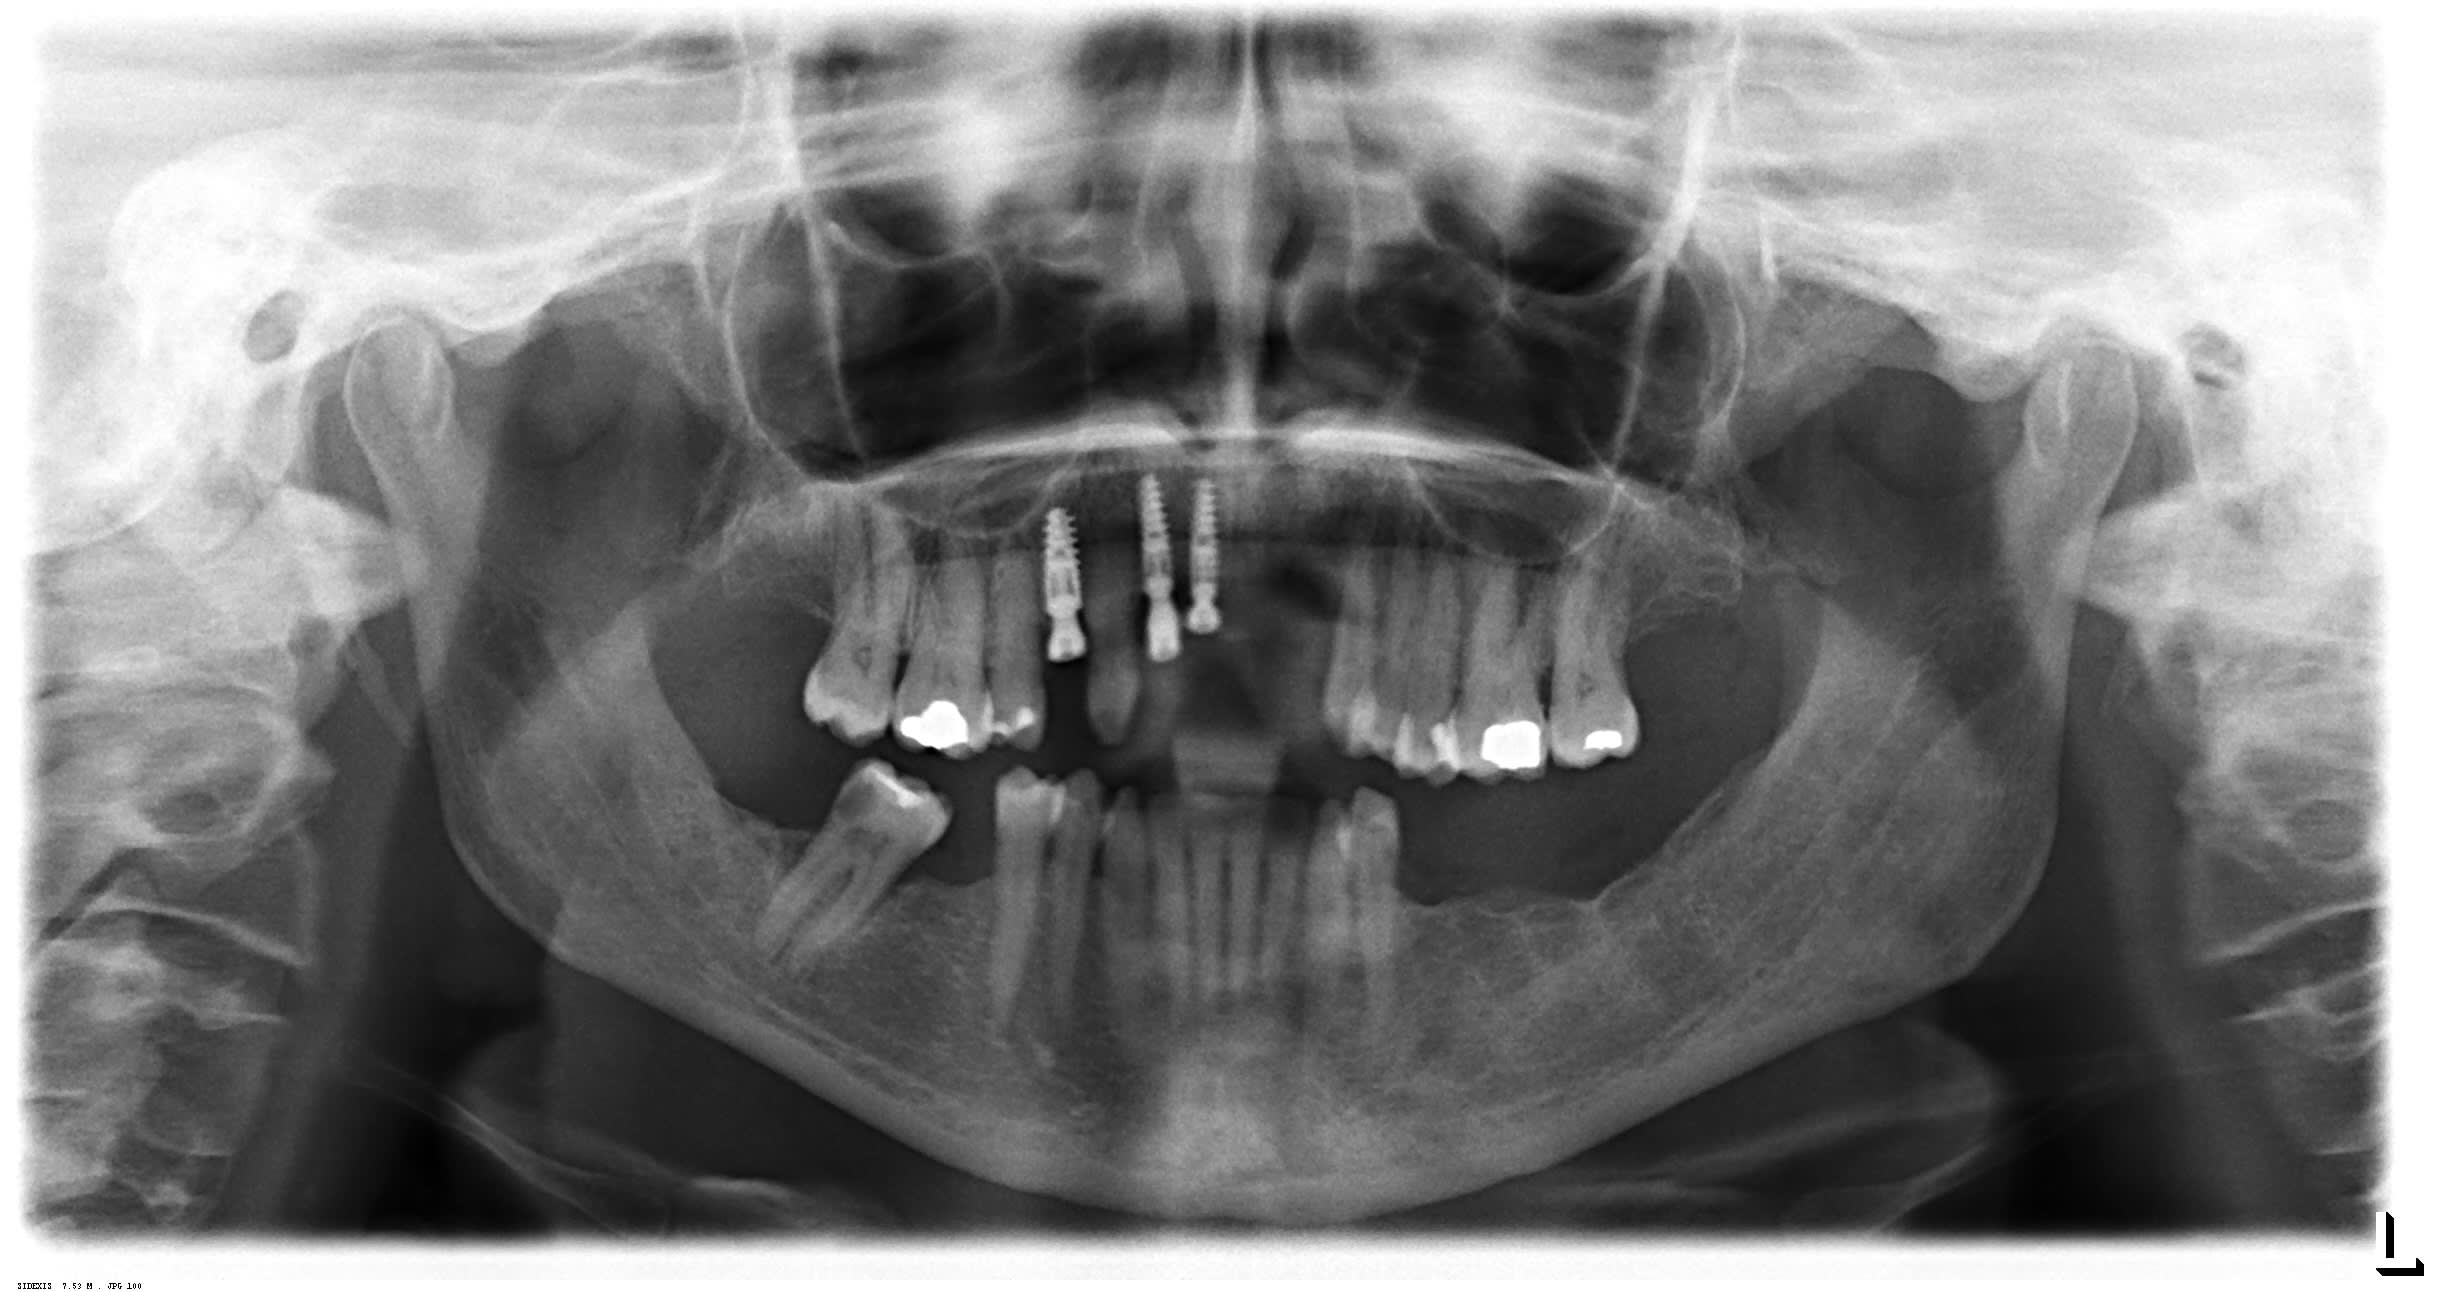

Je reçois une nouvelle patiente :

Pas de soucis de santé mais fumeuse 20 cigarettes par jour

Elle a subi de nombreux échecs implantaires :

- nécrose d'une greffe ramique au niveau de 21/22

- implants déposés puis reposés

Je lui proposerais pour remplacer ses incisives maxillaires :

- sans arrêt du tabac : un stellite pour remplacer ses incisives maxillaires

avec dépose de l'implant en 11 et réenfouissement de l'implant en 12

- avec arrêt du tabac : réaliser un bridge provisoire 13-12-(11/21/22)-23-24 MAIS en mutilant 3 de ses dents (13,23 et 24) mais pour m'assurer d'avoir une prothèse fixe qui me permettra de greffer le secteur 21/22

En effet, le bas étant "plus classique" avec soit PAP ou implants (avec devitalisation 47), je n'en ai pas parlé